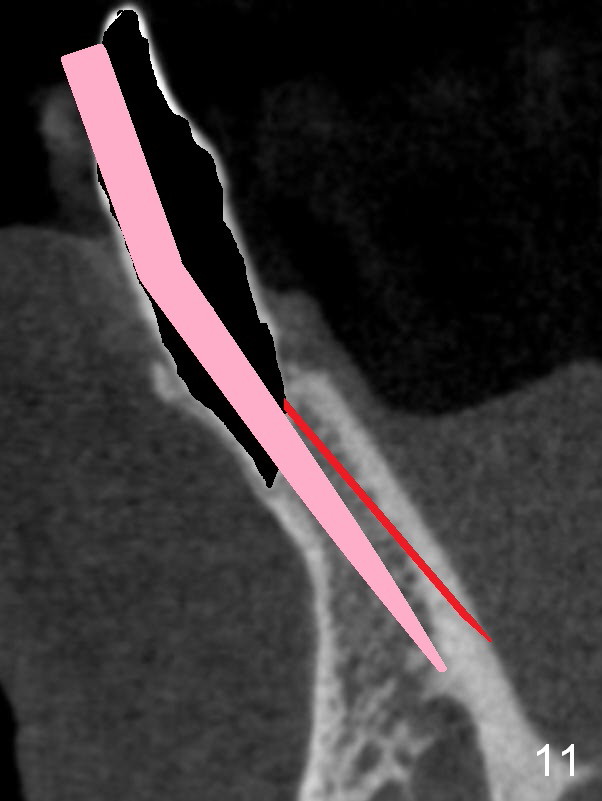

A 74-year-old man has several missing teeth (Fig.1).  His 1st goal is to replace the lower left lateral incisor (Fig.2).  The residual root has an apical lesion (Fig.3 *).  To describe intraop findings, a CT image of a different patient is used (Fig.4 coronal section; B: buccal; L: lingual).  After extraction, the buccal plate is found to be thin and low (Fig.5 arrowheads).  A 1.5 mm pilot drill (Fig.6 red line) is used to initiate osteotomy in the lingual plate of the socket.  Once the drill penetrates the lingual plate, the trajectory changes and the depth is 17 mm from the gingival margin (Fig.7).  A PA is taken (Fig.8); it appears that the osteotomy can be extended more apically.  When the pilot drill extends to 20 mm, there is sudden empty feeling.  The lingual plate has perforated (Fig.9).  A new osteotomy is established buccally (Fig.10 pink).  To avoid buccal plate perforation, especially in the buccal undercut area (>), the coronal end of the drill has to be tilted buccally (<--).  An angled abutment (3x20 mm, 15°) is placed (Fig.11,12).  The abutment is modified (Fig.13,14) to accommodate an immediate provisional (Fig.15,16 P).  Perio dressing is to be applied to prevent the bone graft from getting dislodged buccally (Fig.15).  The dressing is in place 7 days postop (Fig.17).